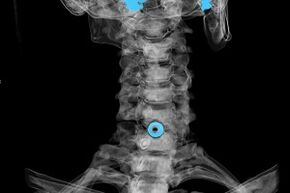

- Моюнчанын омурткасынын моюнчасынын сүрөтүн (магниттик резонансанска сүрөт тартуу). Сөөк структураларын, грниятталган интервферттор дисктерин, алардын өнүгүү багытын көрүүгө мүмкүнчүлүк берген ыкма.